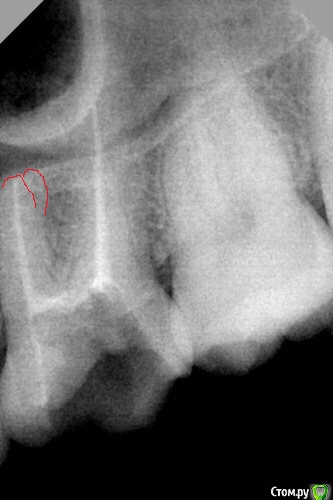

St. Опубликовано 15 августа, 2015 Поделиться Опубликовано 15 августа, 2015 если те лень, тыкните, где? Ссылка на комментарий

Бардо Опубликовано 16 августа, 2015 Поделиться Опубликовано 16 августа, 2015 если те лень, тыкните, где? 2 Ссылка на комментарий

St. Опубликовано 16 августа, 2015 Поделиться Опубликовано 16 августа, 2015 Увидела. Спасибо! Ссылка на комментарий